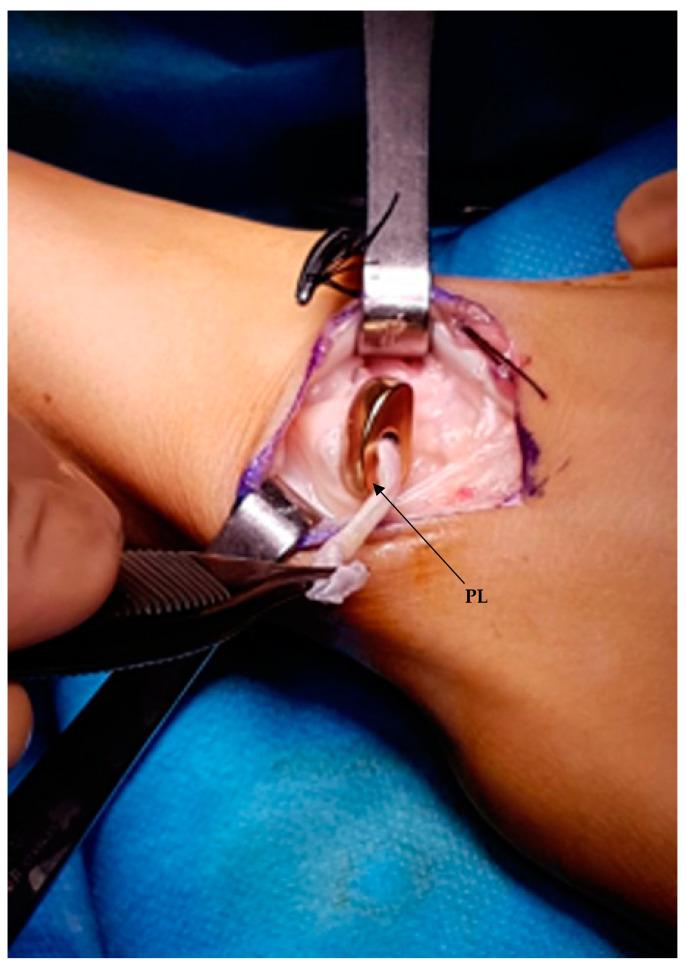

Treatment of scaphoid fracture sequelae is still an unsolved problem in hand surgery. Custom-made 3D-printed titanium partial and total scaphoid prosthesis and scaphoid interosseous ligament reconstruction (SLIL) are performed in cases of non-union and isolated aseptic necrosis of the proximal scaphoid pole and when it is impossible to save the scaphoid bone, respectively. This study aims to evaluate the clinical, functional and radiographic results after these two prosthesis implantations.

舟骨骨折后遗症的治疗仍是手外科尚未解决的问题。对于舟骨不愈合和舟骨近端孤立性无菌性坏死,以及无法保留舟骨的情况,分别采用定制的3D打印钛质舟骨部分和全舟骨假体以及舟骨骨间韧带重建术(SLIL)。本研究旨在评估这两种假体植入后的临床、功能和影像学结果。